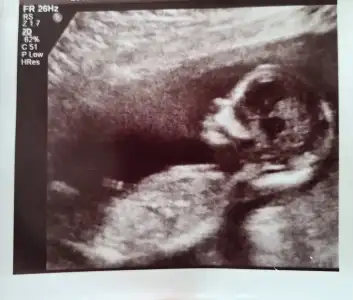

Bu fotoğraftaki benim minik kızııımmmm🥺🥲:KK36:🥰🍀🧡🧿

Bir çok kişi kız demişti galiba.. Bana da öyle gelmişti baştan ama sonra dedim kendimi çok kaptırmayayım. Sağlıkla gelsin yeter ki 🥰🙏🏻 biraz şok olduğum ve çok duygulandığım doğrudur🥲🥲

Doktor gördünüz mü cinsiyeti dedi. Dedik yok. Bakın dedi gösterdi ama tabi yine pek anlamadık 😄 Her yerine baktı yine, baya uzun sürdü. Böbrekleri, kalbi, parmacıkları🥰 Çok şükür sağlıklı 🧿

14+5 olmuş ve 14 cm.

En son yine bir cinsiyeti kontrol etti, dedi ben eminim ama yine bir daha bakiyim karizma cizilmesin 😅 Baktı, fotoğrafıni falan çekti. Dedim erkek olsa zaten görülmez mi.. Yok dedi, bu haftalarda çok net görünmeyebilir. Bakın dedi 2 çizgi var.. Kız dedi 🥰 Biz kızdan yana tecrubesiziz tabi. Ancak hmmm falan dedik 😅

Degismez artık di mi 🙈 Hhihihi😅